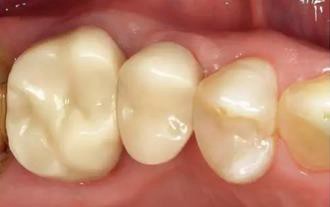

圖11: 戴入口內(nèi)15位點種植體和16自然基牙上的混合陶瓷修復(fù)體冠(頰側(cè)觀)。

圖12:戴入口內(nèi)15位點種植體和16自然基牙上的混合陶瓷修復(fù)體冠((牙合)面觀)。